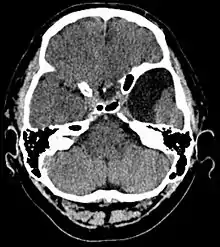

Arachnoid cyst

Arachnoid cysts are cerebrospinal fluid covered by arachnoidal cells and collagen[1] that may develop between the surface of the brain and the cranial base or on the arachnoid membrane, one of the three meningeal layers that cover the brain and the spinal cord.[2] Primary arachnoid cysts are a congenital disorder whereas secondary arachnoid cysts are the result of head injury or trauma.[3] Most cases of primary cysts begin during infancy; however, onset may be delayed until adolescence.[2]

Diagnosis

Diagnosis is principally by MRI. Frequently, arachnoid cysts are incidental findings on MRI scans performed for other clinical reasons. In practice, diagnosis of symptomatic arachnoid cysts requires symptoms to be present, and many with the disorder never develop symptoms.